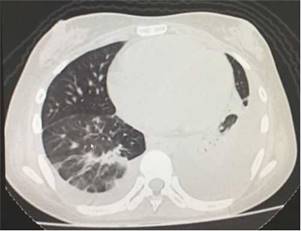

En la radiografía de tórax simple se observó la presencia de derrames pleurales y una imagen sugestiva de consolidación basal izquierda, a pesar de que la paciente no presentaba tos, esputo ni fiebre (fig. 1). En la tomografía simple de tórax se evidenció derrame pleural izquierdo con atelectasia compresiva ipsilateral y bandas parenquimatosas en la base derecha (fig. 2). El ecocardiograma realizado informó de fracción de eyección conservada con una presión sistólica de la arteria pulmonar elevada de 42 mm Hg (Vr. PsAp menor de 36 mm Hg). Se calculó el Systemic Disease Activity Index (SLEDAI) en 21 puntos, considerándose una exacerbación del LES severa. Se inició tratamiento con prednisolona a 30 mg por día, con lo que presentó mejoría de la disnea y de la saturación de oxígeno.

Figura 2 Tomografía simple de tórax con evidencia de derrame pleural izquierdo asociado a atelectasia compresiva ipsilateral y bandas parenquimatosas en la base derecha.